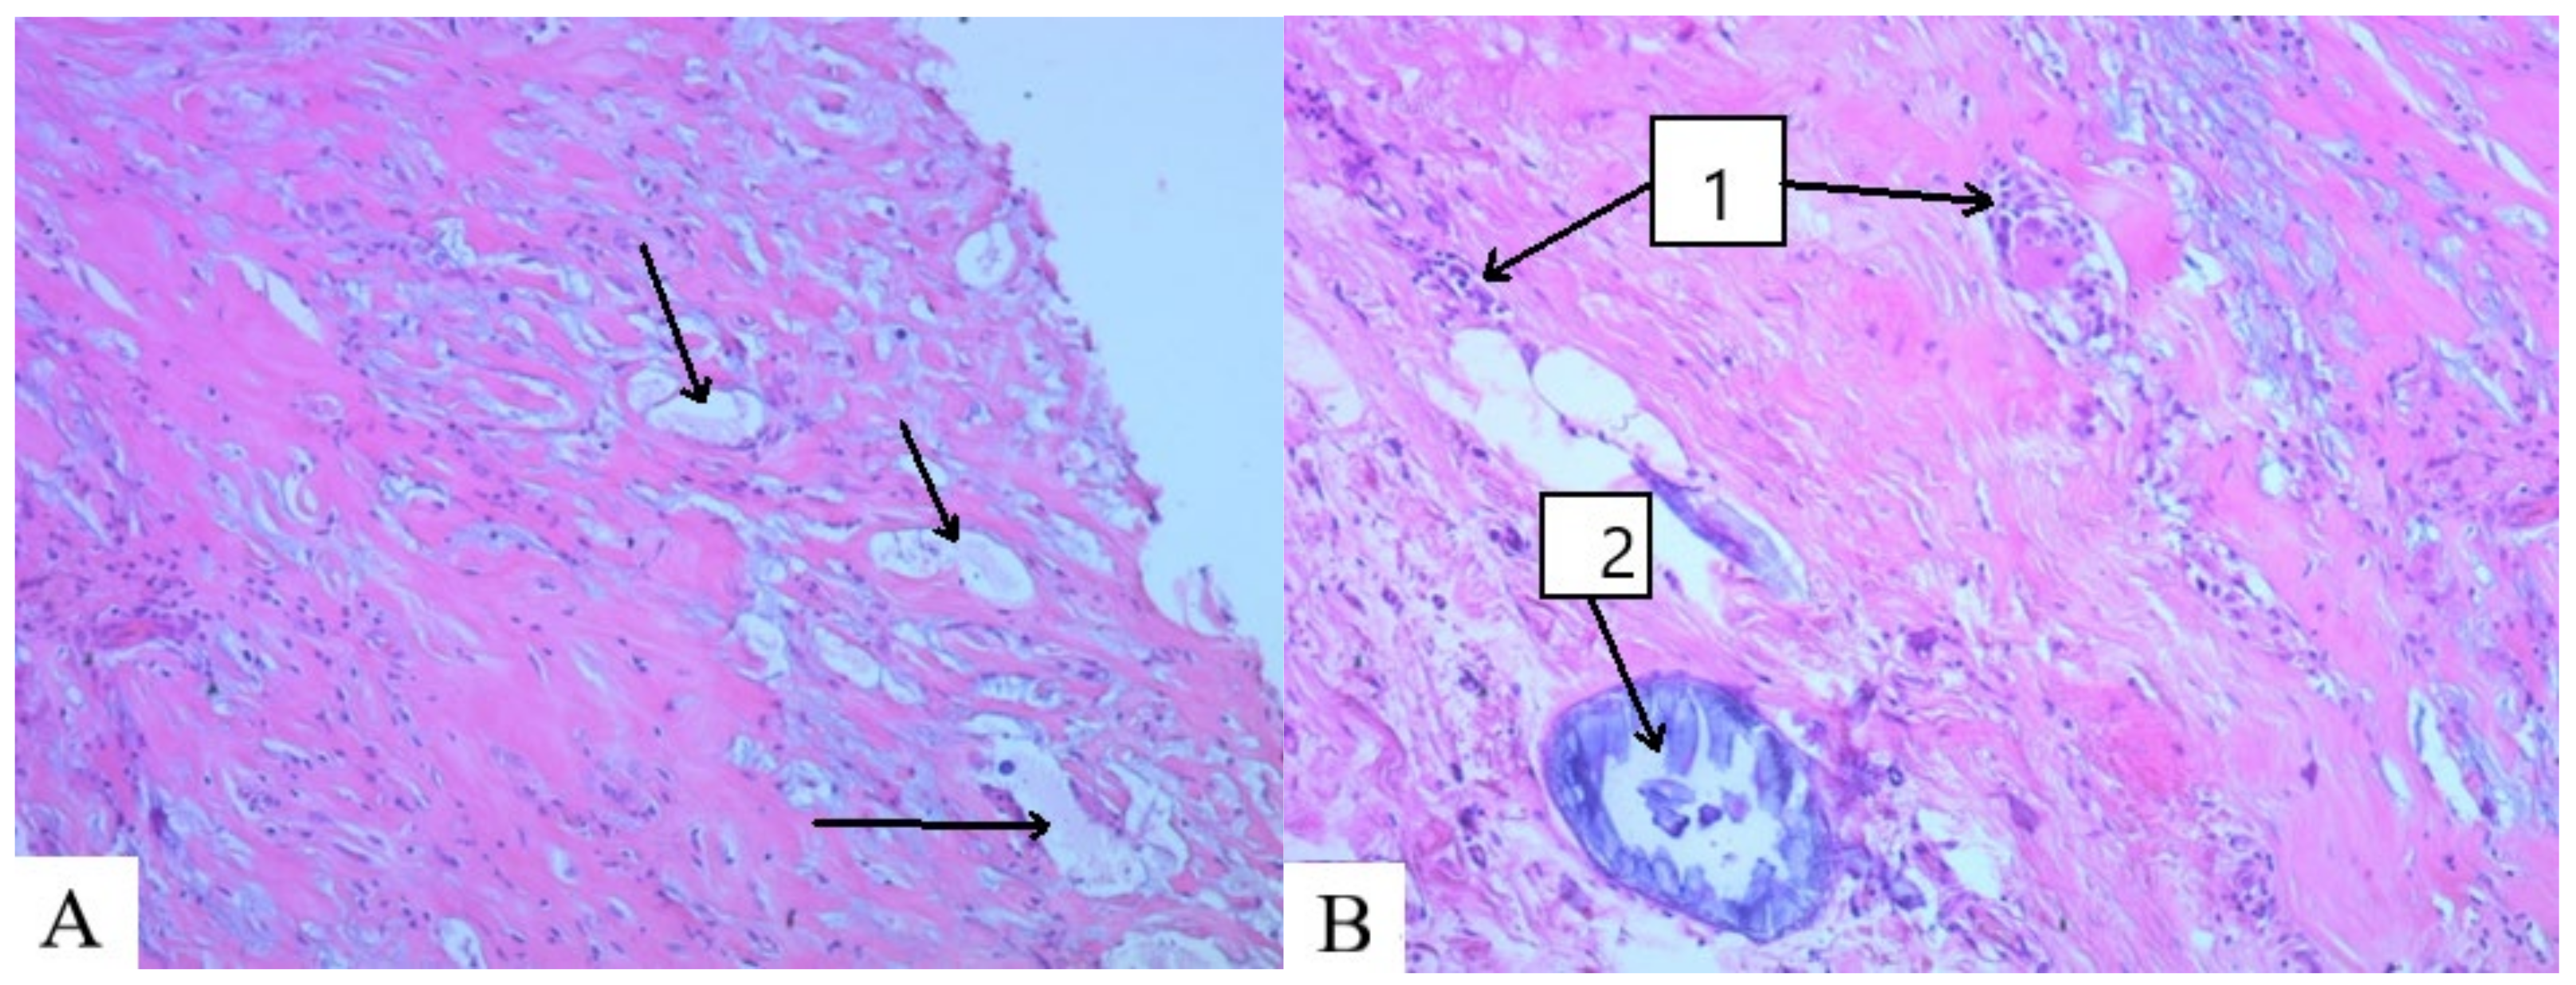

- The interaction of PAA with endogenous and exogenous aldehydes in acidic and slightly acidic media results in the formation of intramolecular cross-linking:

- In this case, intermolecular cross-linking can also occur, resulting in the formation of three-dimensional structures (-CONH-CH2-NHCO-):